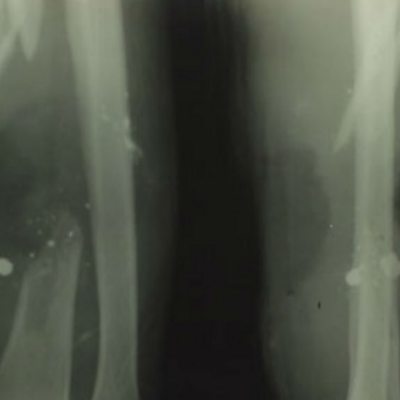

Private Hori Woolgan Jarvis of the 11th Royal West Kent Regiment had his arm shattered by a German sniper’s bullet on 14 June 1917. Many wounded soldiers with such severe injuries and shrapnel would have lost limbs through amputation but Private Jarvis was fortunate to be treated at Tunbridge Wells General Hospital. Here he was treated by the most cutting edge X-ray department outside London. Not only did X-ray make it possible for him to have a bone graft but the success of the treatment enabled him to return to his pre-war occupation as a baker and pastry chef. Sara Parker interviewed his daughter-in-law who found Private Jarvis’s original X-ray plates in the garage when her husband died. She remembers how her father-in-law had been well enough to make the wedding cake for their wedding. Sara was also shown the fragile glass X-ray plates which have been donated to Tunbridge Wells Museum and spoke to hospital archivist John Weeks about the important role of the Salomon family as benefactors. Sir David Lionel Salomon developed the X-ray department in 1915, in memory of his son, Captain David Reginald Salomons who was killed when his troop ship the HMS Hythe sunk off Gallipoli. Location: Tunbridge Wells Hospital, Kent TN2 4QJ Image: Private Hori Jarvis’ X-ray, courtesy of Liz Douglas from Tunbridge Wells Museum